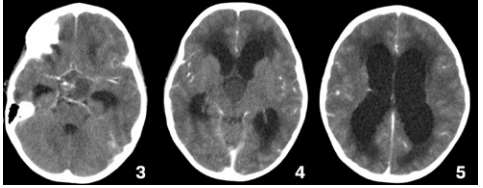

Caso clínico 3 para as questões 27 e 28.

Seguem, abaixo, as imagens de TC de crânio sem e com contraste da paciente, com índice de Evans de 0,41.

Como se calcula o índice de Evans que foi de 0,41 e o que se fazer pela urgência nesse caso, respectivamente?